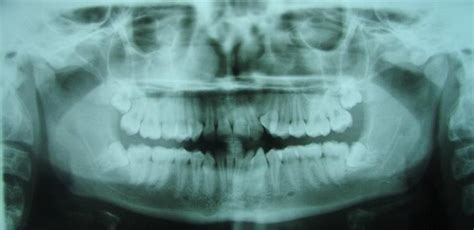

Registros Radiográficos Pretatamiento y Cefalometría

La ortopantomografía inicial (fig. 4) muestra una dentición mixta, iniciando el segundo período de recambio, con obturaciones a nivel de 16 y 26 y cóndilos mandibulares simétricos.

Figura 4. Ortopantomografía pretratamiento.